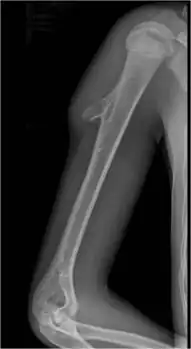

Osteochondroma arising from the large long bone of lower leg, near the knee -

Osteochondroma arising from long bone of the upper arm, near shoulder